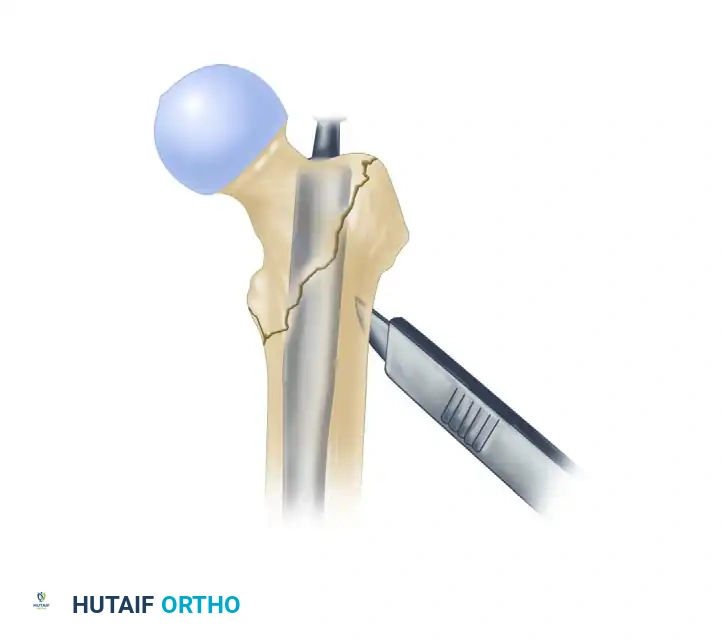

2. Proximal Canal Preparation

Once the guide pin is perfectly localized under fluoroscopy, the proximal femur must be prepared to accommodate the trapezoidal proximal geometry of the nail.

- Introduce the 12.5-mm entry reamer / 16-mm channel reamer combination through the soft tissue guide (entry portal tube) over the guide pin.

- Insert the channel reamer to the level of the lesser trochanter. The entry portal tube features a positive stop to prevent over-insertion.

Insertion of the entry reamer/channel reamer combination to the level of the lesser trochanter.

- For a long InterTAN nail, remove the entry reamer and guide pin at this time, leaving the channel reamer in place to protect the proximal soft tissues and guide subsequent instrumentation.